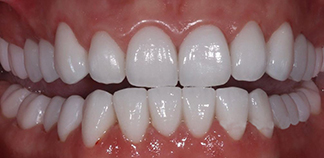

Жалоба на стираемость зубов.

Как лечили

Проведено тотальное протезирование зубов коронками и винирами E-max.